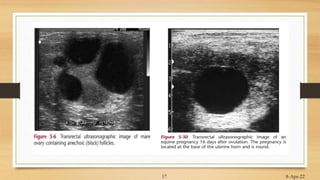

Ultrasonographic Method

• B – mode ultrasound

• Transrectal or linear probe

• Land mark Urinary bladder (Grayish)

• By Ultrasound …..day 16 pregnancy

• Ideally…..At day 30-35…accurate results

• Frequency mostly….5MHz -7.5 MHz